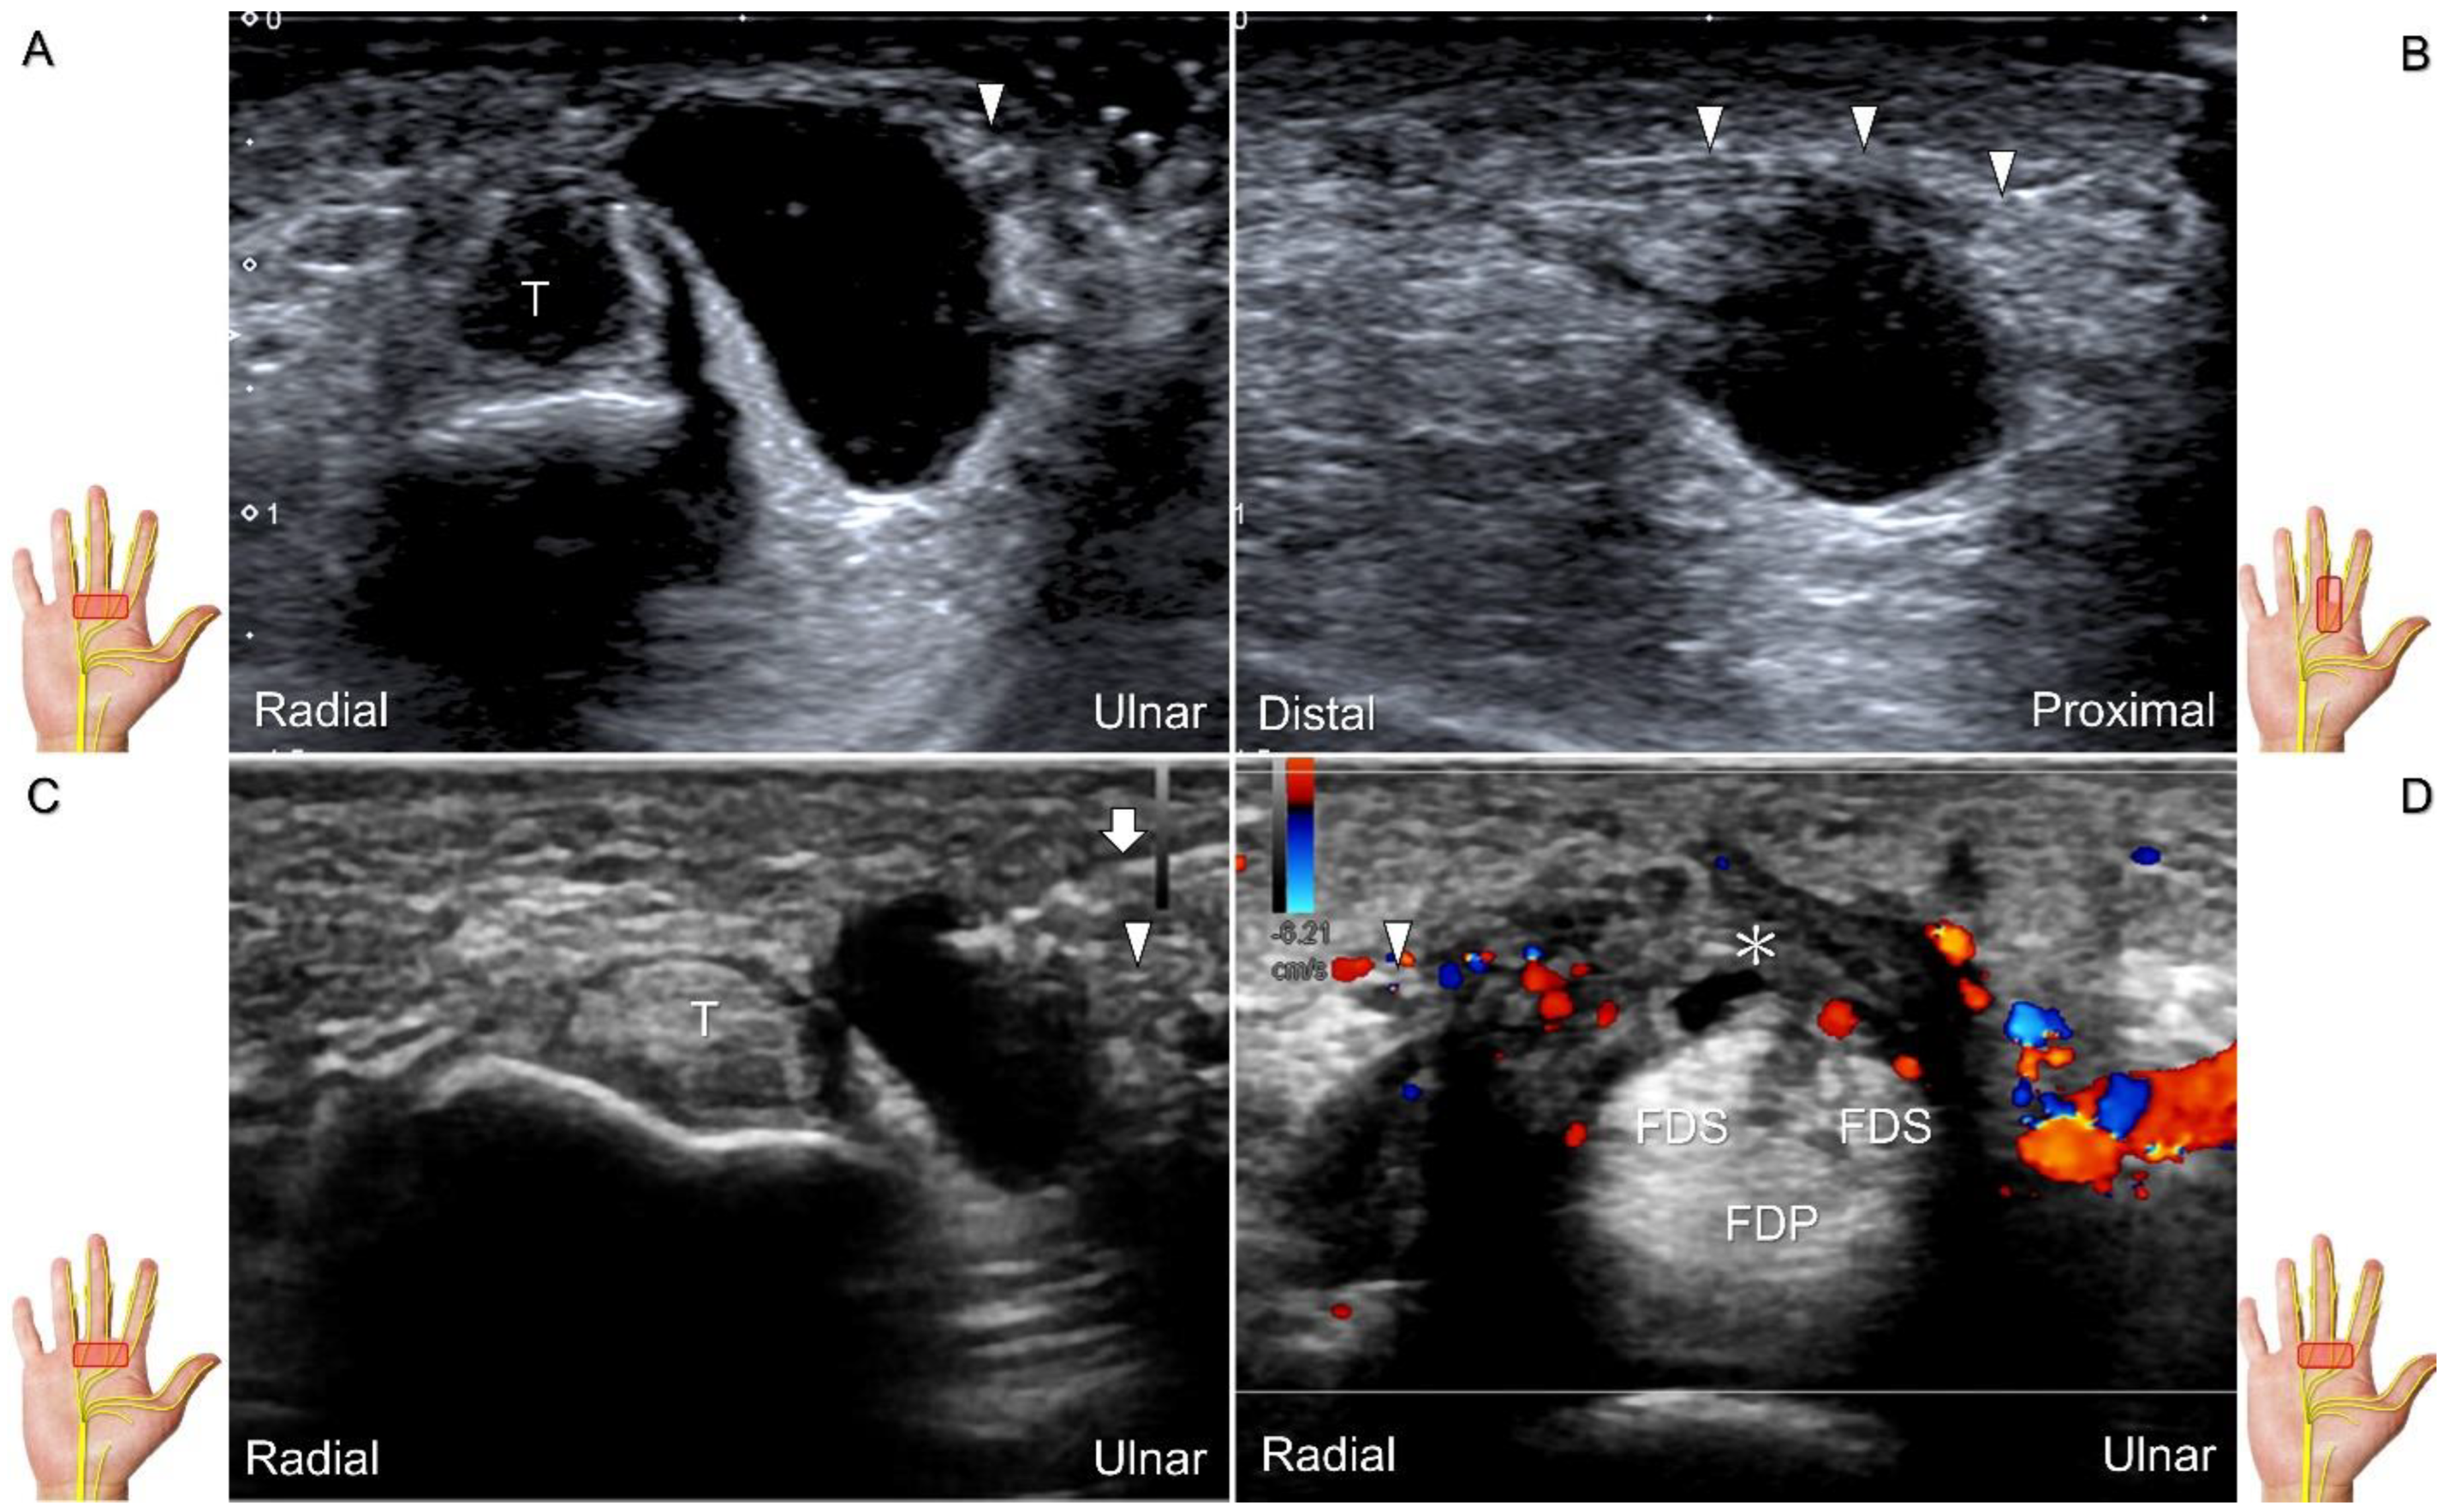

Carpal tunnel syndrome is the most common entrapment neuropathy whereby the median nerve is entrapped by various causes, like hypertrophy of the flexor retinaculum (Figure 2C,D) and compression from the accessory muscles, swollen tendons, ganglions, and bony fractures within the tunnel. Ultrasonographic changes encompass swelling proximal to the entrapment site (Figure 3A), flattening over the entrapment site (Figure 3B), intraneural hypervascularity (Figure 3C), and focal loss of the trimline pattern (Figure 3D).

Figure 3. Sonographic images of patients with carpal tunnel syndrome, showing focal swelling proximal to the compression site (A), flattening at the compression site (B), intraneural hypervascularity (C), and loss of the trimline pattern (D). White arrowhead: focal swelling of the median nerve; asterisk: flattening of the median nerve; black arrowheads: intraneural hypervascularity of the median nerve; white arrows: loss of the trimline pattern of the median nerve; black arrow: thickened flexor retinaculum.